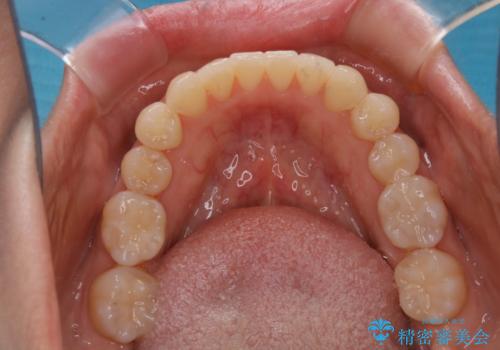

矯正治療とセラミック治療が終了後のPMTC

- 矯正治療とセラミック治療の総合治療が終了したため、クリーニングをしっかりとしてからメンテナンスに入りたいとのことでした。PMTC30分コースを行いました。

矯正治療が終わり、せっかくきれいになった歯並びも、虫歯・歯周病などになってしまっては元も子もありません。

矯正治療やセラミックなどによる被せ物の治療終了のタイミングではクリーニングを行い、汚れや着色の除去、歯と歯の間・歯と歯肉との境目などのケアをしっかりすることをおすすめしています。

ご自身での歯ブラシ・セルフケアを行うと同時に、定期的なクリーニング(PMTC)を行うことで、いつまでも健康な歯を保つことができます。